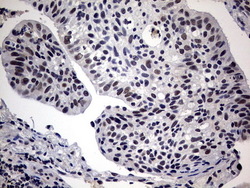

- IHC of paraffin-embedded Adenocarcinoma of Human ovary tissue using anti-SAP30BP mouse monoclonal antibody. (Heat-induced epitope retrieval by 10mM citric buffer, pH6.0, 120°C for 3min).

- IHC of paraffin-embedded Carcinoma of Human lung tissue using anti-SAP30BP mouse monoclonal antibody. (Heat-induced epitope retrieval by 10mM citric buffer, pH6.0, 120°C for 3min).